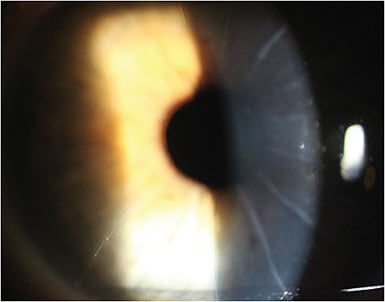

Entering MRx in both eyes is a low level of hyperopia with astigmatism in both eyes. Anterior segment exam is remarkable for 8 cut RK OD and 16 cut RK OS (Figures 5 and 6). Heidi has visually significant anterior cortical cataracts in both eyes. Posterior segment exam is unremarkable in both eyes.